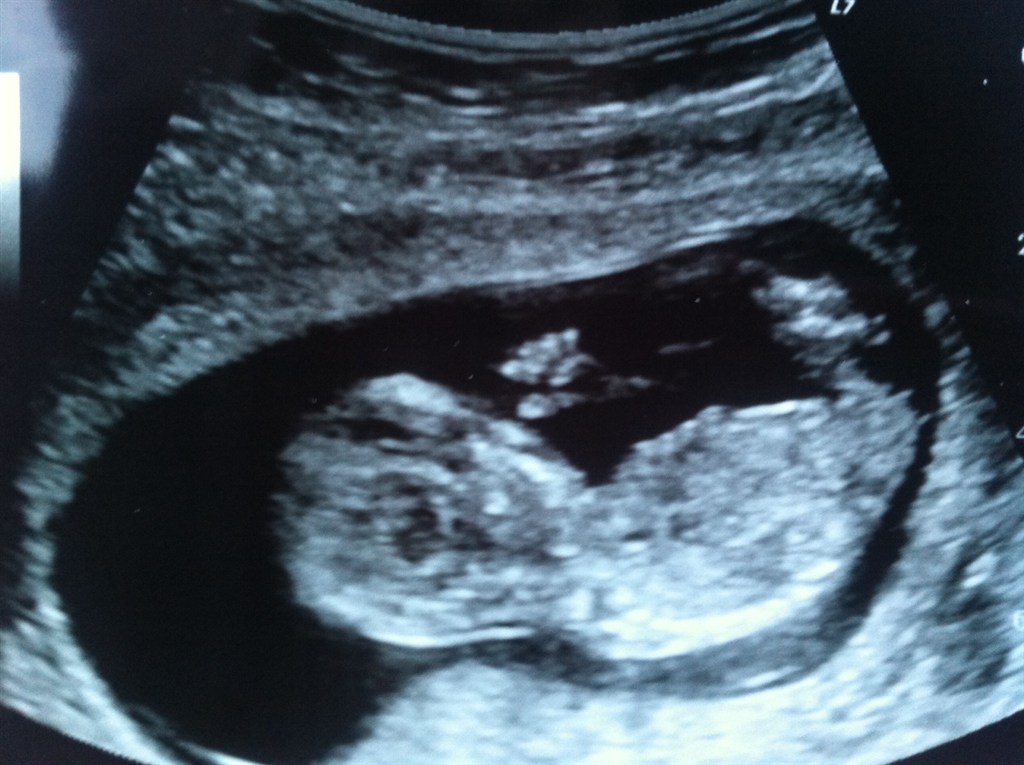

Jeg har i dag været til NF scanning... og baby har det helt som den skal!!! Fik tallet 1:20972 og en melding om at der ikke er noget galt med lillen...

Jeg er bare SÅ glad, og hold da op en lille vildbasse jeg har i maven

Vedhæftede fotos (klik for at se i fuld størrelse)